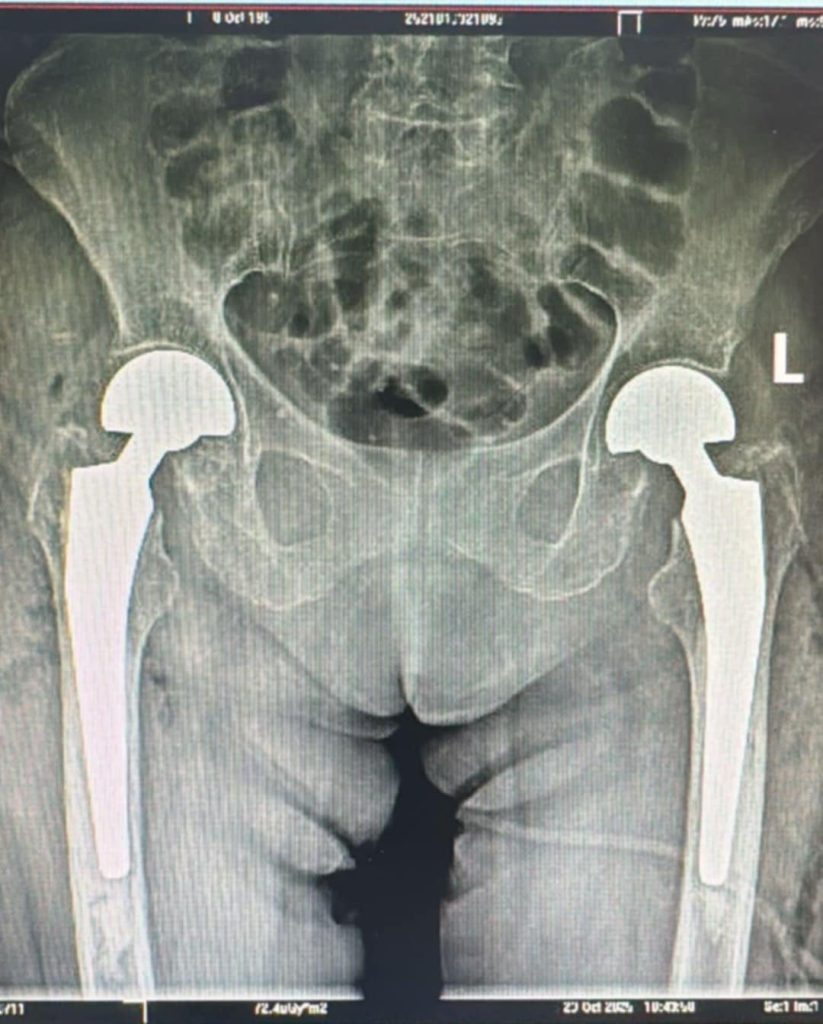

O procedură chirurgicală majoră și extrem de rar întâlnită a fost realizată în premieră la Spitalul Clinic Județean de Urgență Sibiu, unde echipa de ortopedie a efectuat o artroplastie parțială de șold bilateral, intervenție realizată într-un singur timp operator. Cazul a vizat o pacientă de 73 de ani, diagnosticată cu fractură bilaterală de col femural, patologie severă ce necesită intervenție rapidă și expertiză avansată.

Echipa medicală a decis efectuarea unei artroplastii parțiale de șold bilateral cu proteze bipolare cimentate, realizată concomitent pe ambele șolduri – o intervenție cu grad înalt de dificultate și intensitate operatorie.

Particularitatea acestui caz constă atât în diagnosticul rar, cât și în realizarea simultană a intervenției pe ambele șolduri.